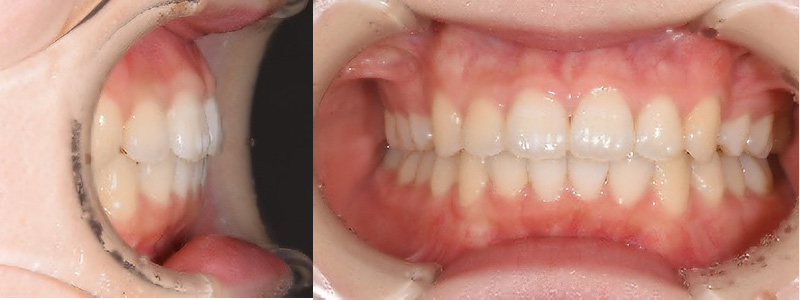

- 治療名

- 矯正

- 治療内容

- 前歯前突改善のため上顎左右4本を抜歯し、マウスピースのみで矯正。

- 患者様

- 10代女性

- 治療期間

- 1年6ヶ月

- 費用

- ¥935,000

- 治療に対するリスク

- 後戻り

- 執刀医

- Dr.村尾